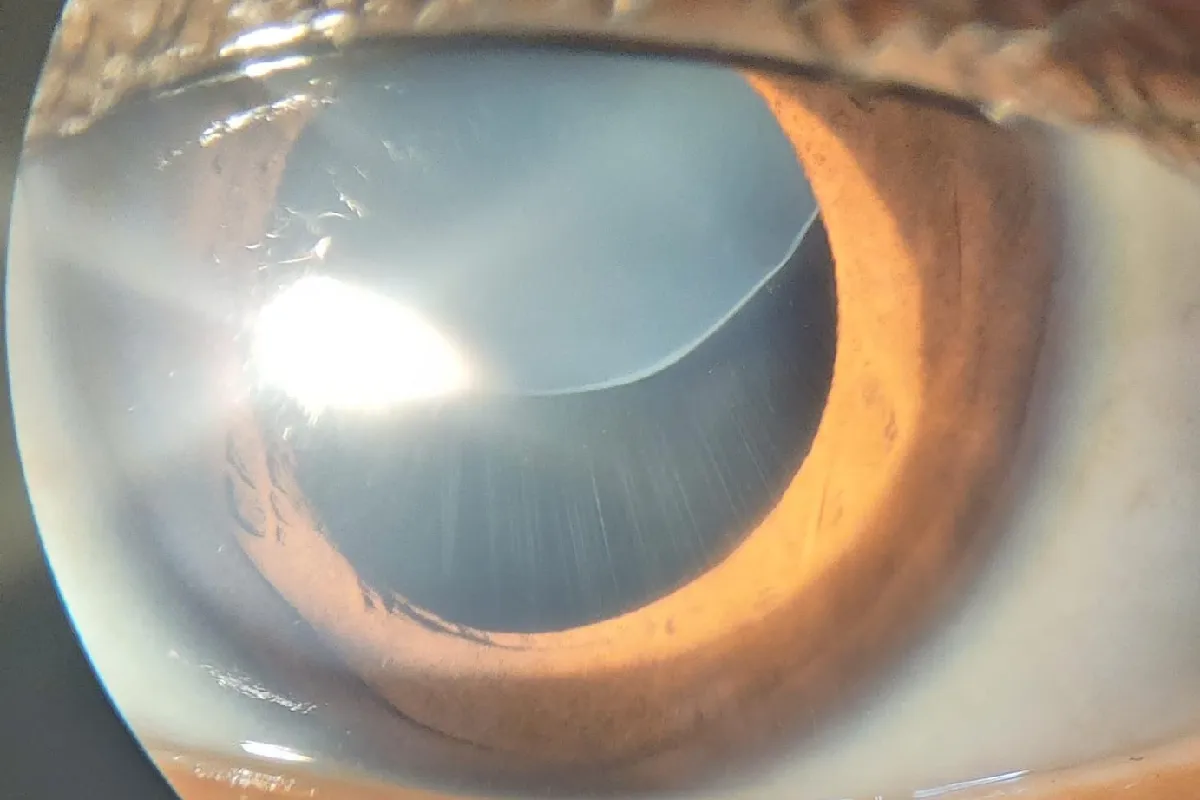

We handle complex cataract cases including mature cataracts, post-traumatic cataracts, subluxated lenses, and cataracts with associated ocular conditions. Our approach ensures optimal outcomes with enhanced visual recovery.